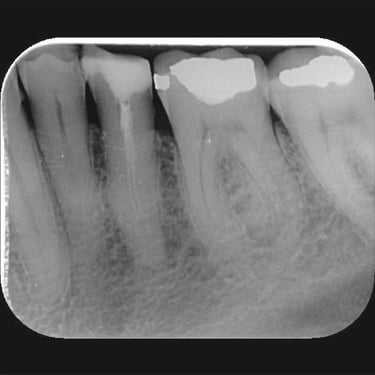

CASOS CLÍNICOS ENDO

Abaixo você encontra fotos de alguns dos tratamentos realizados.